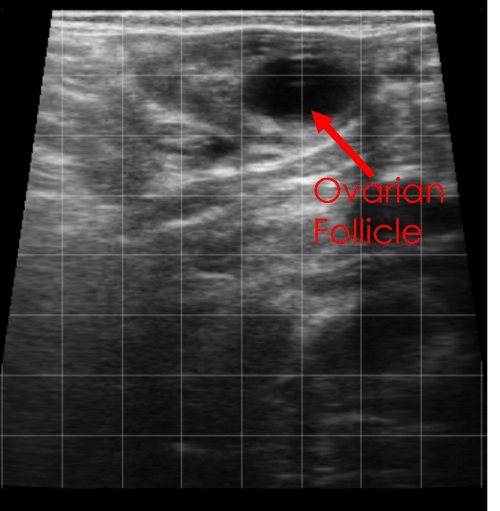

In this image of an ovary, a single, larger follicle can be seen.